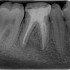

Devitalizzazione Molare Inferiorie

Caso eseguito dal

Dr. Luca Schiavio